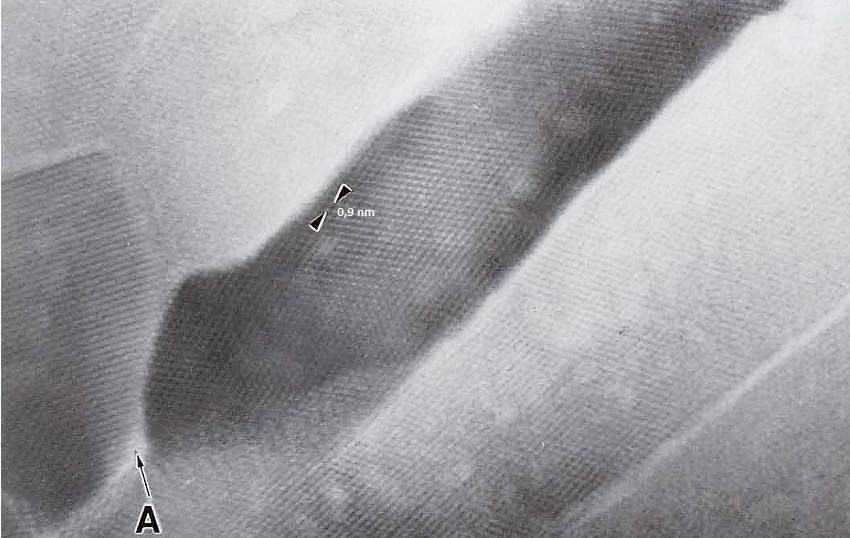

The infective trypomastigote form of Trypanosoma cruzi, the causative agent of Chagas’disease, is able to penetrate a large number of cells through an endocytic process with formation of a parasitophorous vacuole. A few hours after penetration the trypomastigote form gradually transfomiates into the spherical amastigote form (Review in De Souza 1974). During this process a porin-like macro- molecule is released by the parasite (Andrewset al. 1990) gradually lysing the membrane lining the vacuole so that after a few hours the amastigote form is in direct contact with the structures and organdíes of the host cell (De Carvalhoand De Souza 1994). There are very few information on the changes which take place in the host cell cytoplasm during the evolution of the inlracellular parasitism. Here I report observations made on the distribution of glycogen partióles of heart muscle cells infected with T. cruzi.